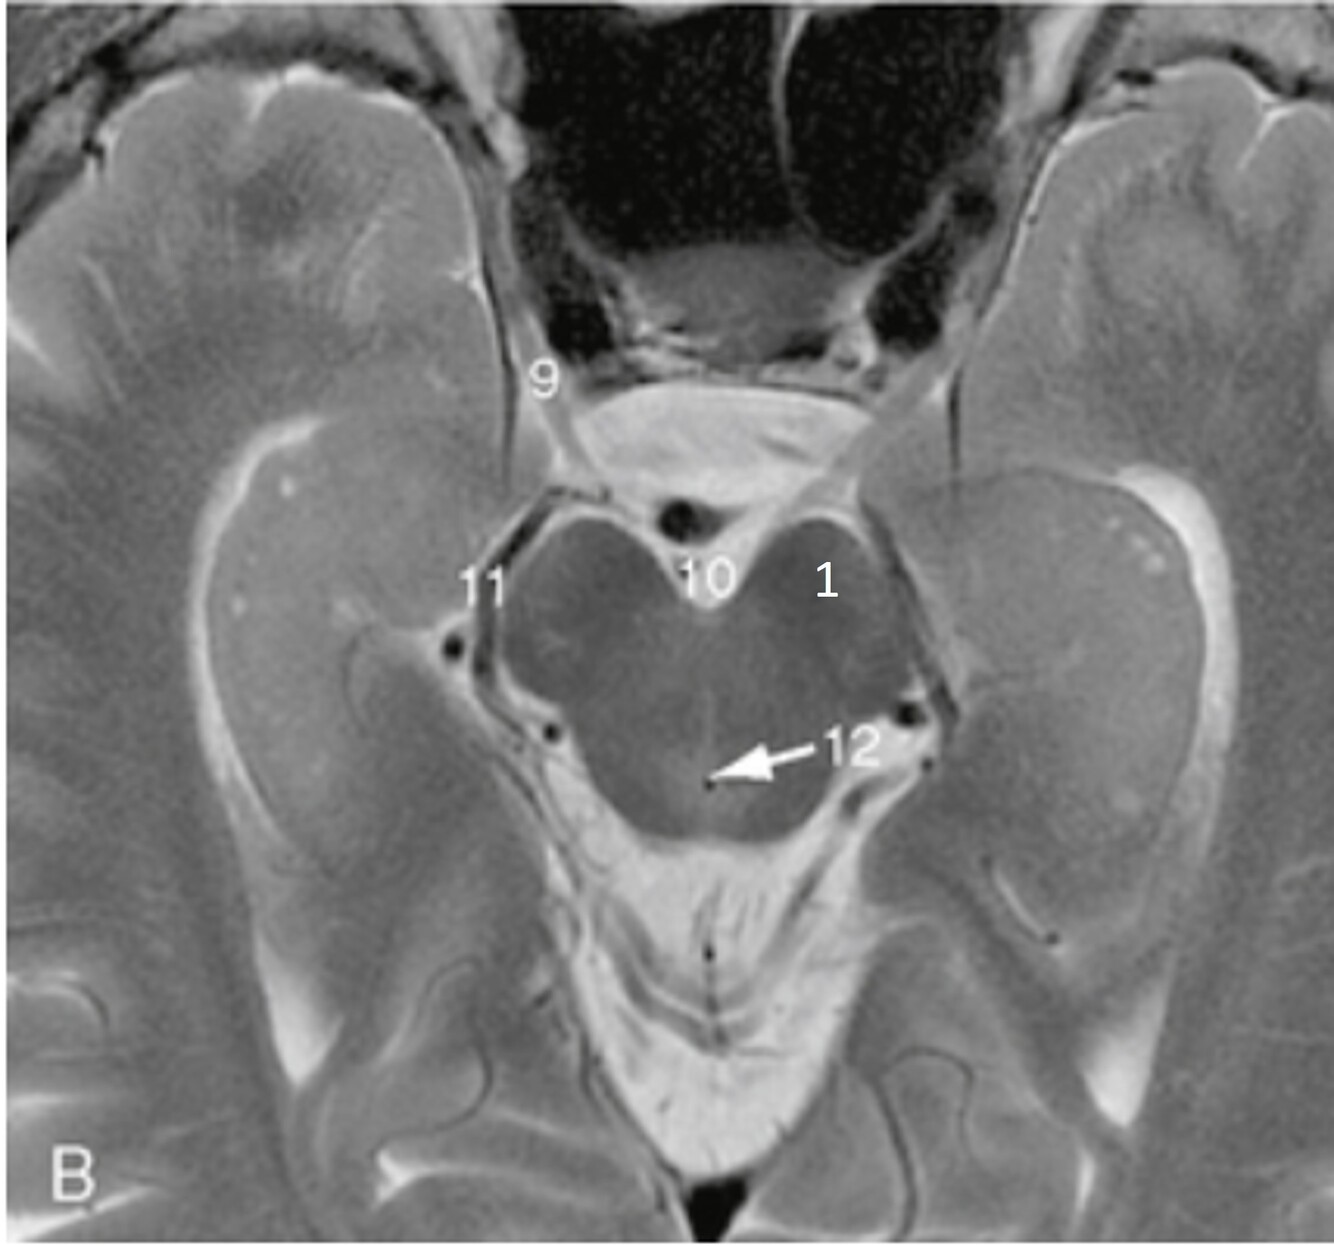

Q

Label 7-11

A

7=Rt Internal carotid artery

8=Optic chiasm

9=Pituitary gland

10-Lt lateral ventricle

11=Lt Cavernous sinus